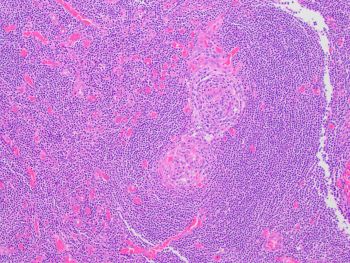

A 45-year old man with a history of PTC, tall cell variant (PT3b N1a M0), s/p total thyroidectomy, central neck lymph node excision and radioactive iodine therapy, presents with new neck mass. Figures a & b show FNA of the mass.